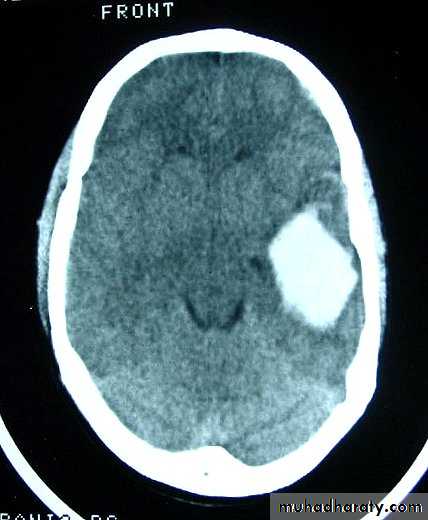

a. Extradural Haematoma

Usually due to TRIVIAL trauma.

Source of bleeding(Haematoma):

1. Linear squamous temporal skull fractures with laceration of a branch of the underlying middle meningeal artery.

2. Fractured bone edges.

3. Laceration of the dural sinuses.

CT scan will show biconvex or lens configuration.

They are more likely to occur in the younger age group.

An extradural haematoma is a neurosurgical emergency.

Surgical treatment by evacuation of haematoma via CRANIOTOMY.

Care must be taken in assessing patients with linear fractures crossing the middle meningeal territory.